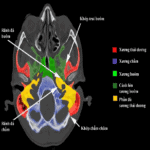

Giải Phẫu CT Sọ Não | Bài giảng CĐHA

Giải phẫu cắt lớp vi tính sọ não:

– Giải phẫu thùy não.

– Giải phẫu nhân xám trung ương.

– Giải phẫu não thất.

– Bể não và khoang dưới nhện.

– Giải phẫu động mạch, tĩnh mạch não.

– Giải phẫu lát cắt Axial sọ não.